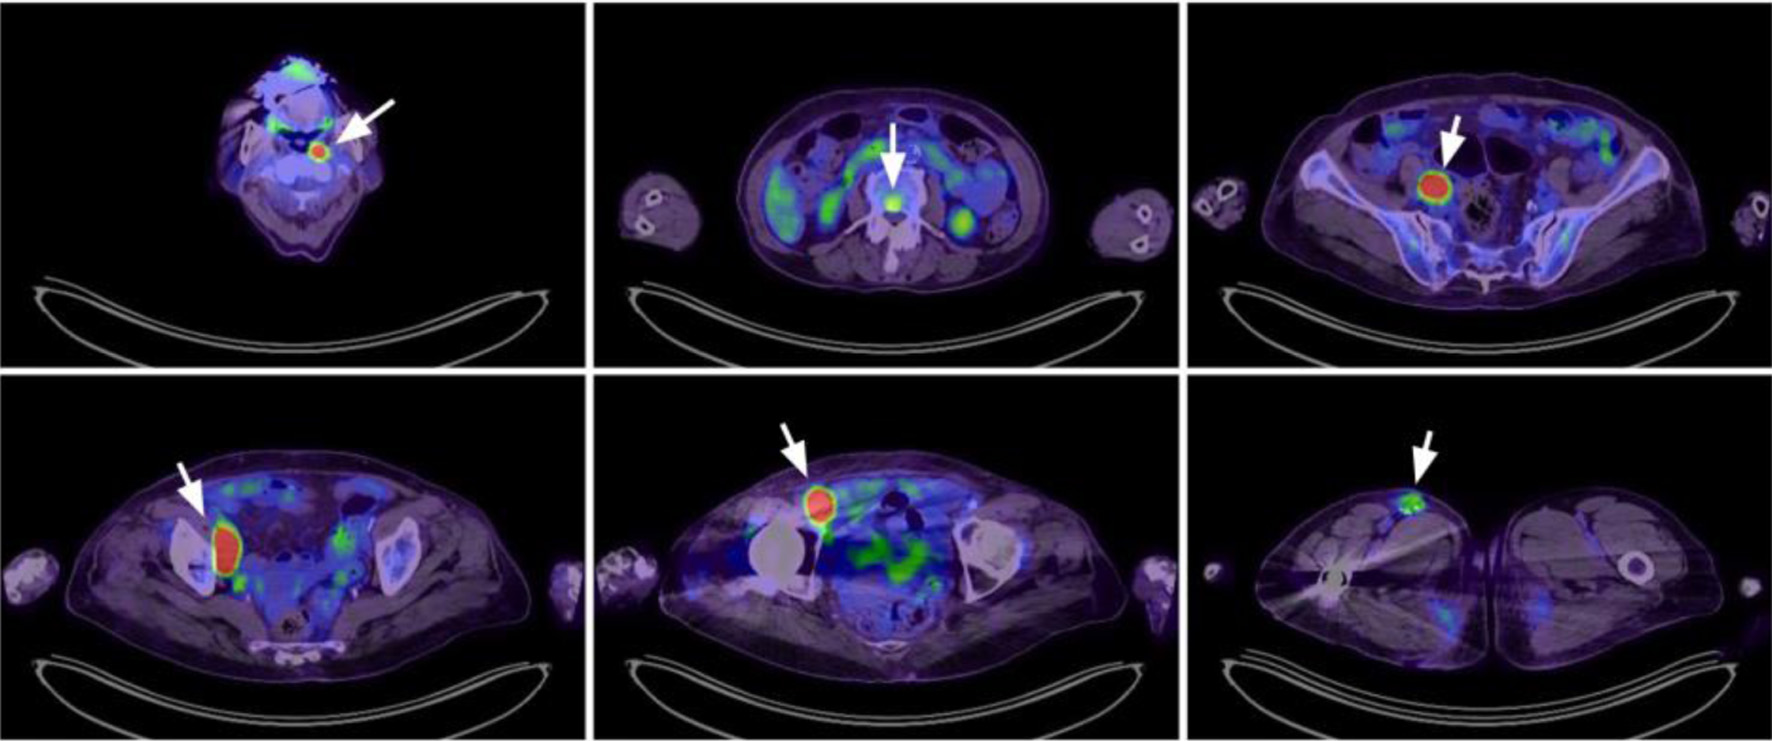

A 79-year-old Asian woman was initially presented with an enlarging right femoral mass for 2 months. An excisional biopsy confirmed the diagnosis of DLBCL, with immunohistochemical expression of MUM-1, BCL-6, BCL-2, and c-MYC. A positron emission tomography (PET) scan revealed stage IV disease with multiple bone involvements (Fig. 1). Bone marrow study revealed 0.1% of clonal B cells that expressed CD19, CD20, and surface kappa light chain. Based on her age, extranodal involvement, and stage IV disease, her revised International Prognostic Index (R-IPI) was 3.

Figure 1. Positron emission tomography scan at diagnosis revealed lymphoma involvement at multiple nodal areas (left nasopharyngeal, right iliac, right femoral) and vertebral spine (arrowheads).